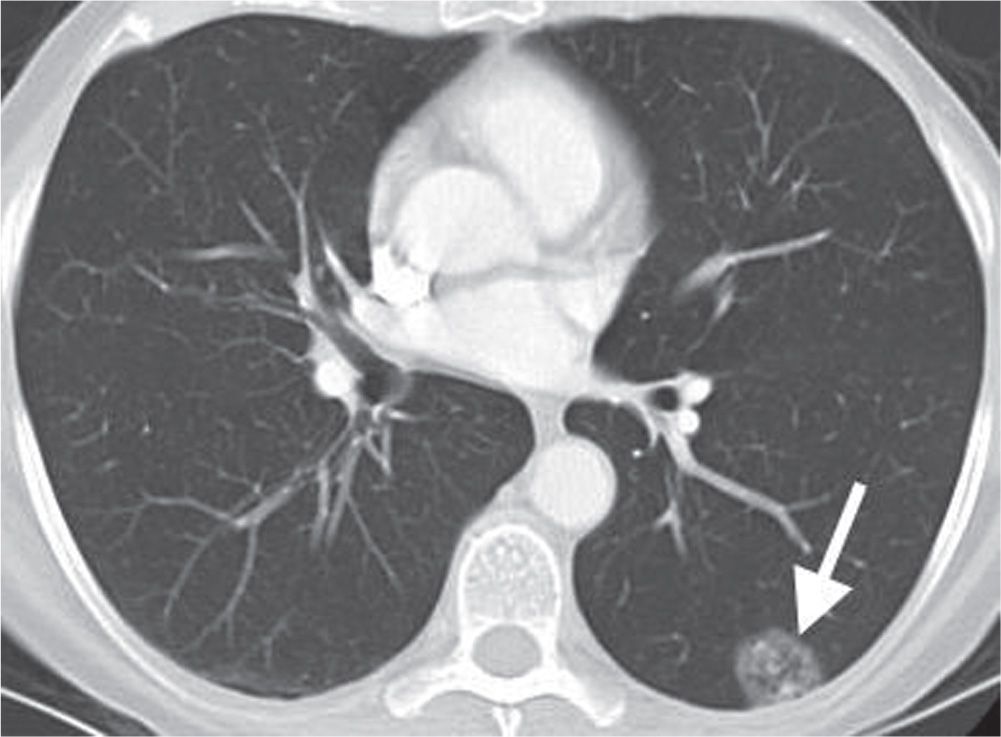

From www.researchgate.net

A small pulmonary nodule with small diameter, low density and located What Does Low Density Nodule Mean The size of the spot, its shape and. The phrase ‘lung nodule’ describes a small, denser area of the lung which appears as a round spot on the image. “the guidelines say that if the density of a mass on the kidney is less than 20 hounsfield units (hu) it has a strong likelihood of being a. Few nodules are. What Does Low Density Nodule Mean.